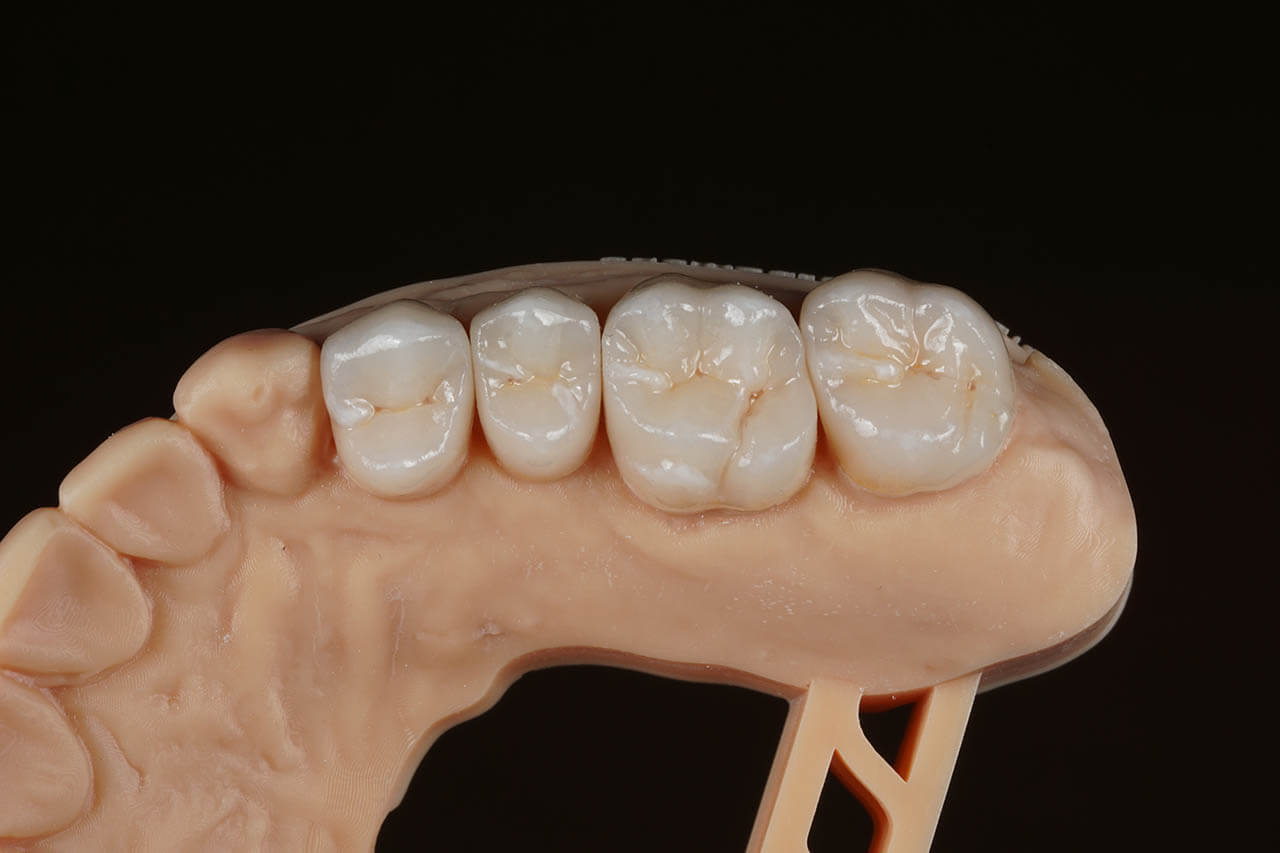

Dental prosthetics deals with filling gaps in the dentition and reconstructing damaged teeth. It is a good choice for anyone who in the past did not properly care for their teeth and as a result could not maintain their natural dentition or lost teeth due to illness or an unfortunate event. A properly chosen partial or full denture allows for the recovery of an aesthetic smile, good well-being, and self-confidence. Prosthetics at the Z Wieży clinic in Władysławowo offers you a wide range of modern prosthetic solutions, from which everyone can choose something tailored to their needs and expectations regarding the final result. Our experienced, highly qualified doctors are ready to provide assistance and good advice. To ensure the highest quality and aesthetics of restorations, we have for years cooperated with a renowned prosthetic laboratory.

Types of prosthetic restorations used at the Z Wieży clinic:

• Porcelain and all-ceramic prosthetic crowns;

• Acrylic and zirconia crowns;

• Dental bridges and dentures.

Our prosthetic work